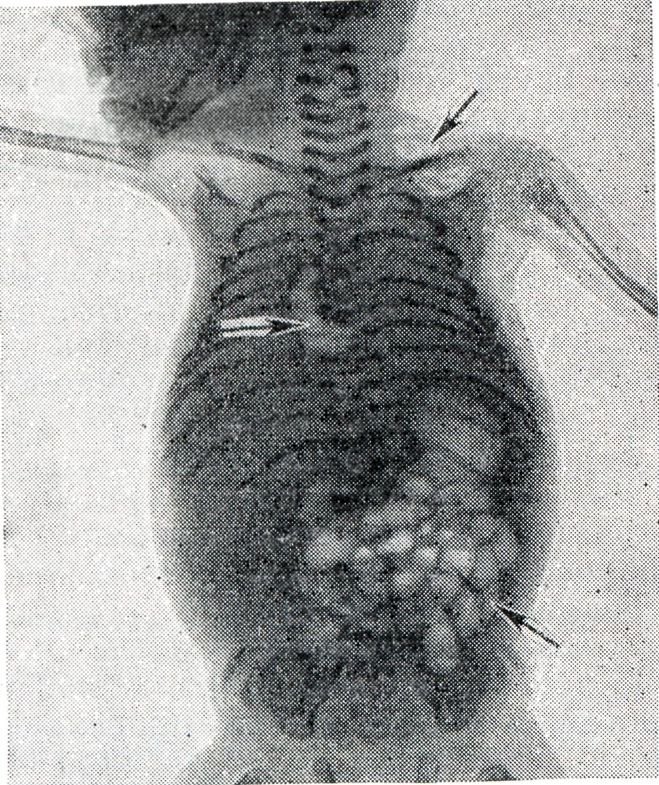

Выявление газа в полостях сердца плода всегда затруднительно из-за наличия газов в кишечнике матери, но газ без труда обнаруживается при рентгенографии мертворождённого. Присутствие газовых скоплений в сердце и крупных сосудах объясняют посмертным внеутробным гниением в том случае, если уже имеются значительно выраженные наружные признаки трупного разложения, когда газы скапливаются и в подкожной клетчатке (рисунок 2).